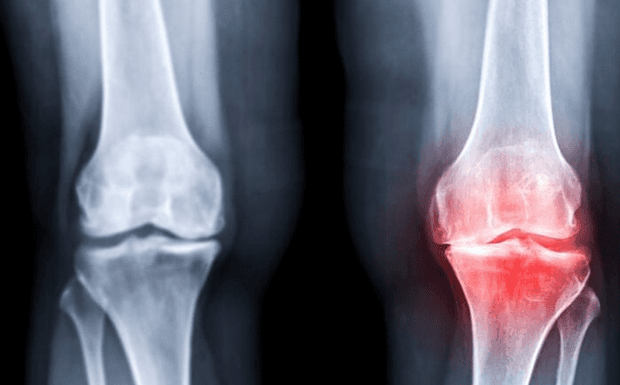

Osteoarthritis vs Rheumatoid Arthritis Explained: Understanding the Key Differences That Matter

Arthritis is one of the most common causes of pain and disability in the UK, affecting millions of people across all age groups. Yet despite how widespread...